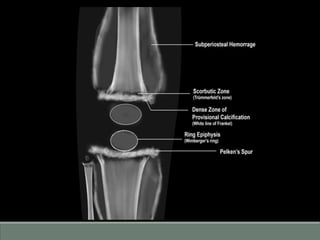

Rickets Scurvy

Epiphyseal centres are invisible or

indistinct

Epiphysis is sharply marginated by

sclerotic rim (Wimberger’s sign)

Loss of zone of provisional calcification

adjacent to metaphysis, thus having a

faint and irregular line (Fraying)

Zone of proviosional calcification at

metaphysis is dense giving a “ White line

of Frenkel’s sign”

Not found Trummerfeld zone and Pelken’s spur

seen

Subperiosteal layer may be found but less

marked effect.

Sub-periosteal hemorrhage due to

capillary fragility giving rise to periosteal;

elevation.

Differential diagnosis Rickets Scurvy Epiphysealcentres are invisible or indistinct Epiphysis is sharply marginated by sclerotic rim (Wimberger’s sign) Loss of zone of provisional calcification adjacent to metaphysis, thus having a faint and irregular line (Fraying) Zone of proviosional calcification at metaphysis is dense giving a “ White line of Frenkel’s sign” Not found Trummerfeld zone and Pelken’s spur seen Subperiosteal layer may be found but less marked effect. Sub-periosteal hemorrhage due to capillary fragility giving rise to periosteal; elevation.

• #23 Beneath the zone of provisional calcification, there is evidence of lucent zone related to lack of mineralized osteoid (Trummerfeld zone). Lateral projection of white line of frenkel may lead to formation of spur or marginal cleft.